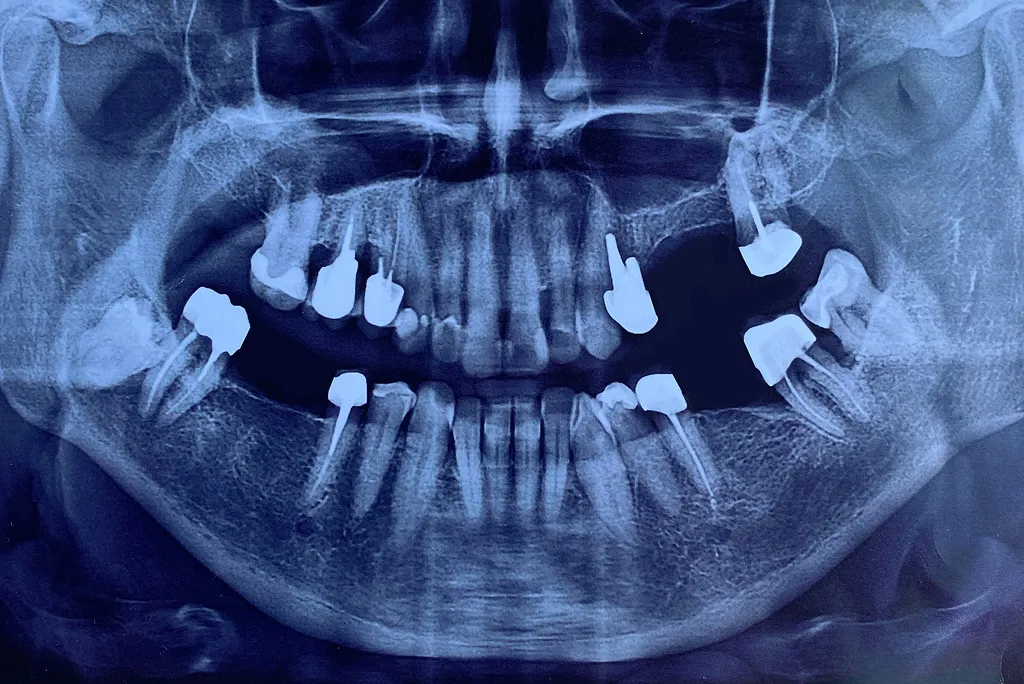

• Panoramic: These capture a single, wide image of your entire mouth—all the teeth, the upper and lower jaws, sinuses, and jaw joints (TMJ). These are usually taken less frequently, perhaps every 3-5 years, to assess wisdom teeth, bone structure, and comprehensive planning.